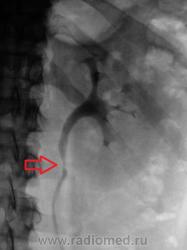

Почки контурируются в типичном месте, обычной формы и размеры. R-позитивных уроконкрементов в проекции мочевыносящих путей на обзорной урограмме не выявлено. ЧЛС контрастированы синхронно, не расширены. Мочеточники контрастированы, левый просматривается на всем протяжении, в нижней 1/3 незначительно стойко расширен, оттеснен кверху и вправо (хотя возможен такой вариант расположения устьев мочеточников - к сожалению правый мочеточник не визуализируется т.е. несчем сравнить). В мочевом пузыре, слева от срединной линии, дефект наполнения с четкой неровной границей.

Мы решили сразу после исследования сделать томографию мочевого пузыря.

Валентин Львович томограмки у вас хорошие получились, а как вы это расценили? Лично мне кажется это от давления из вне, а по поводу УЗИ, разве оно не входит в алгоритм обследования пациентов с МКБ и почечной коликой у вас в больнице?